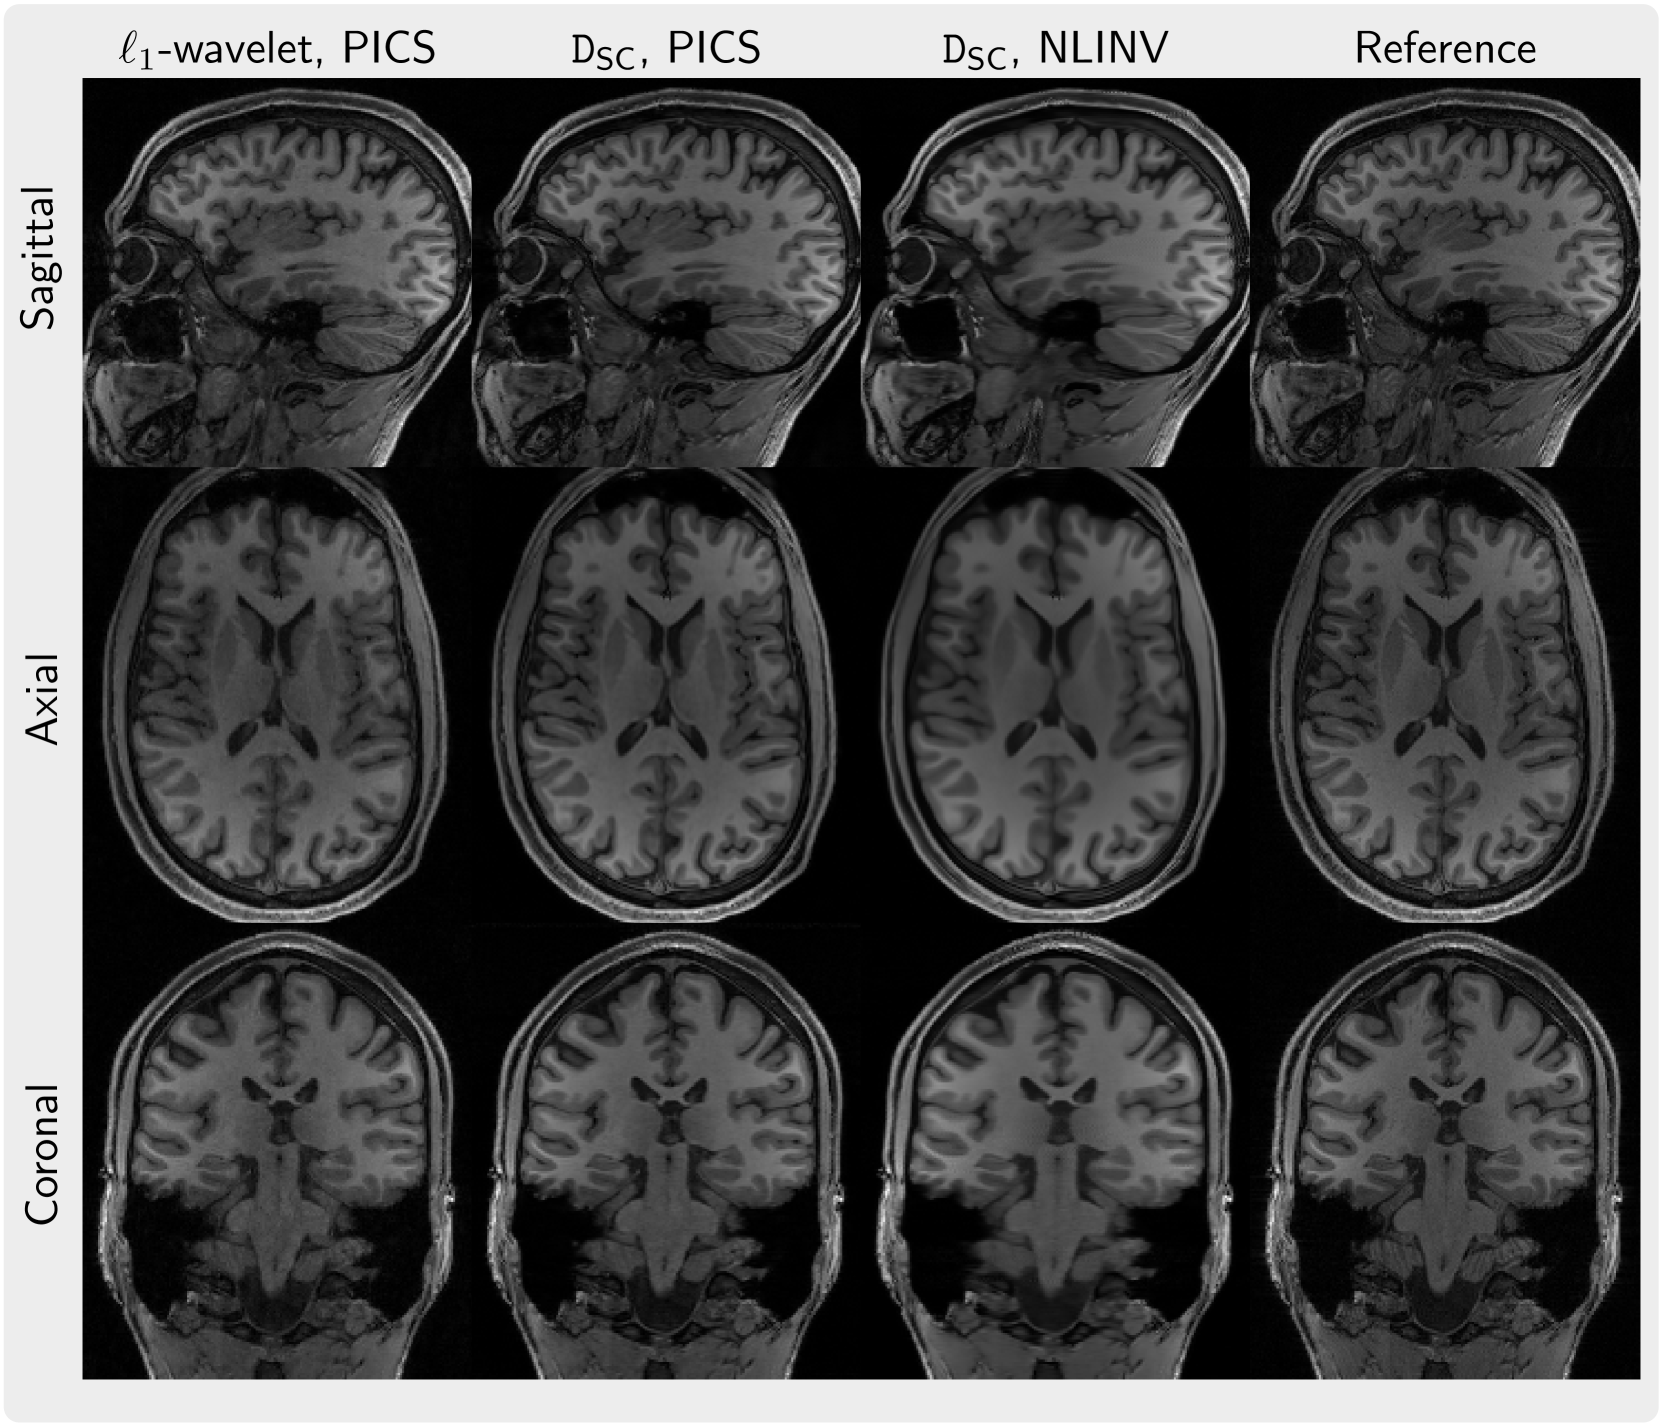

As an example, Figure 8 presents three slices in the sagittal, axial, and coronal planes for a 3D volume reconstructed using the diffusion prior DSC using PICS and NLINV in comparison to 1subscript1\ell_{1}roman_ℓ start_POSTSUBSCRIPT 1 end_POSTSUBSCRIPT-wavelet regularization and a reconstruction by coil combination of Fourier-transformed fully-sampled k-space data. By visual inspection, the 1subscript1\ell_{1}roman_ℓ start_POSTSUBSCRIPT 1 end_POSTSUBSCRIPT-regularized images appear to have reduced sharpness compared to the images regularized by the diffusion prior DSC while also having more noise.

Refer to caption

Figure 8: Slices in three orientations (Sagittal, Axial, Coronal, from top to bottom) from a 3D volume reconstructed using PICS from 8.2x-undersampled k-space with Poisson-disc sampling with 1subscript1\ell_{1}roman_ℓ start_POSTSUBSCRIPT 1 end_POSTSUBSCRIPT-wavelet regularization and the diffusion prior DSC and using NLINV with diffusion prior DSC (from left to right).